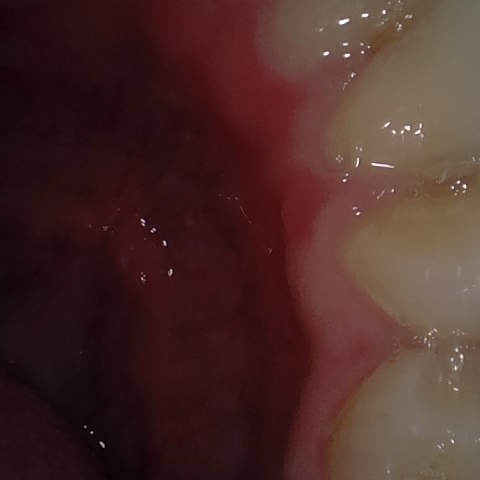

Annotated as "Bad"